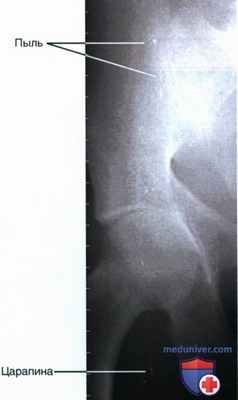

Артефакты рентгенограмм - это искусственные посторонние образования на пленке, возникшие во время ее хранения, экспонирования или после фотообработки. Наличие артефактов определяется во время детального изучения рентгенограмм на негатоскопе, но предварительно рекомендуется рассмотреть обе поверхности в отраженном свете под косым углом. Такой прием позволяет обнаружить возможные дефекты пленки: отпечатки пальцев, царапины, пятна, нанесенные в процессе проявления, фиксирования, промывки или сушки рентгенограмм.

Прозрачные точки и пятна на пленке возникают, когда на эмульсионный слой попала пыль. Осаждение пыли на эмульсии происходит при сушке пленки в горизонтальном положении.

РИСУНОК 18 Компьютерная рентгенография тазобедренного сустава в ПЗ проекции. На изображении выявляются артефакты, вызванные наличием на ПИ частиц пыли и царапин.

• Частицы пыли и грязи на поверхности люминофорной пластины приведут к появлению на изображении небольших белых точек или изогнутых белых линий (рис. 18)

• Избавиться от частиц пыли и грязи можно протерев запоминающую пластину. Избавиться от царапин можно только заменив пластину